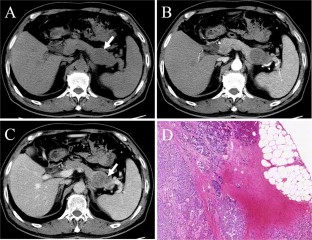

Fig. 4